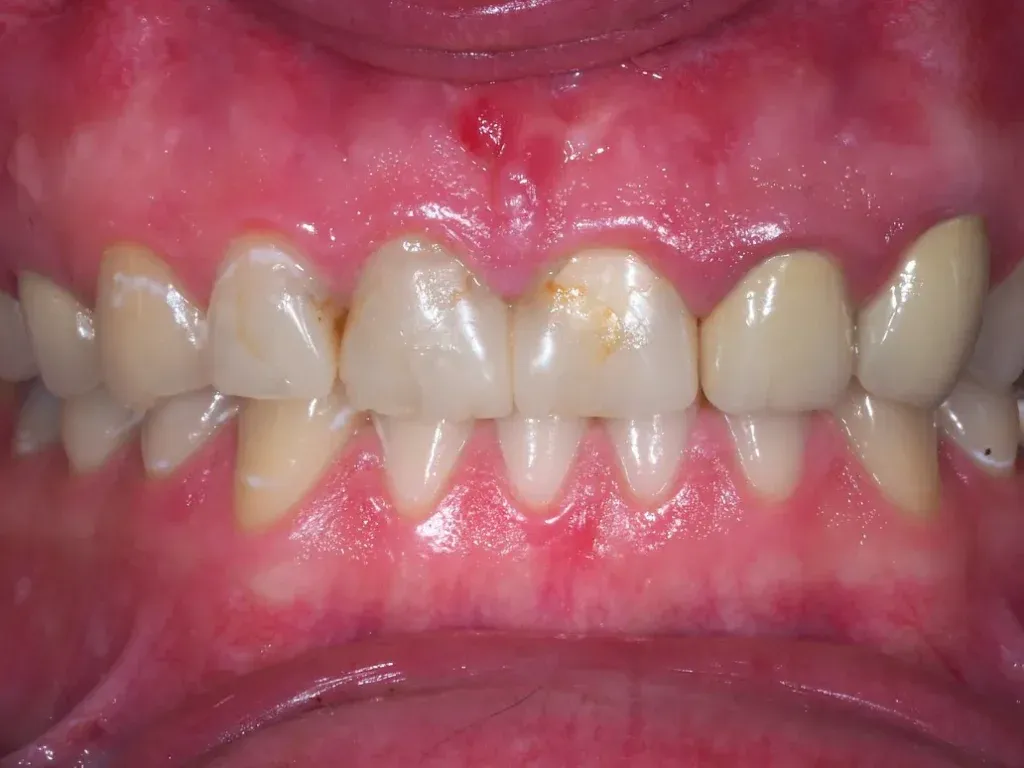

Często pacjenci mają problem z odróżnieniem zdrowych dziąseł od tych objętych stanem zapalnym. Widząc różne odcienie różu czy sporadyczne krwawienie, nie zawsze wiedzą, czy to powód do niepokoju. Pamiętam, jak jeden z moich pacjentów był zaskoczony, gdy pokazałem mu na zdjęciu, jak powinny wyglądać zdrowe dziąsła. To właśnie wizualne porównanie jest często najbardziej przekonujące. Zdrowe dziąsła są jasnoróżowe, jędrne i ściśle przylegają do zębów, tworząc delikatne, scalloped marginesy. Nie krwawią podczas szczotkowania ani nitkowania i nie są bolesne. Natomiast dziąsła objęte stanem zapalnym, jak już wspominałem, są zaczerwienione (od jaskrawoczerwonego do sinofioletowego), obrzęknięte i miękkie w dotyku. Bardzo łatwo krwawią, nawet przy delikatnym podrażnieniu, a w zaawansowanym stadium mogą być bolesne i odsłaniać szyjki zębowe. Obraz, który umieściłem wcześniej, doskonale ilustruje te różnice, pomagając wizualnie ocenić stan swoich dziąseł.

W mojej praktyce często obserwuję, że pacjenci zgłaszają się do gabinetu dopiero wtedy, gdy objawy zapalenia dziąseł stają się naprawdę uciążliwe. Tymczasem pierwsze sygnały są zazwyczaj bardzo charakterystyczne, choć łatwo je przeoczyć. Najczęściej pojawia się krwawienie dziąseł, zwłaszcza podczas szczotkowania zębów, nitkowania, a czasem nawet podczas jedzenia twardych pokarmów. Dziąsła mogą również stać się zaczerwienione ich kolor zmienia się z naturalnego, jasnoróżowego na jaskrawoczerwony, a nawet sinofioletowy. Często towarzyszy temu obrzęk, sprawiający, że dziąsła wydają się spuchnięte i grubsze niż zwykle. Dodatkowo, pacjenci skarżą się na nieświeży oddech, czyli halitozę, oraz nieprzyjemny posmak w ustach, który jest efektem namnażania się bakterii. Co ważne, we wczesnym stadium choroby te objawy zazwyczaj nie są bolesne, co niestety usypia naszą czujność.

- Wyraźna opuchlizna dziąseł: Dziąsła są widocznie powiększone, mogą zakrywać większą część zębów.

- Intensywnie czerwony lub siny kolor dziąseł: Zamiast zdrowego różu, dziąsła przybierają ciemniejszy, niezdrowy odcień.

- Regularne i obfite krwawienie: Krwawienie pojawia się nie tylko przy szczotkowaniu, ale także spontanicznie lub przy lekkim dotyku.